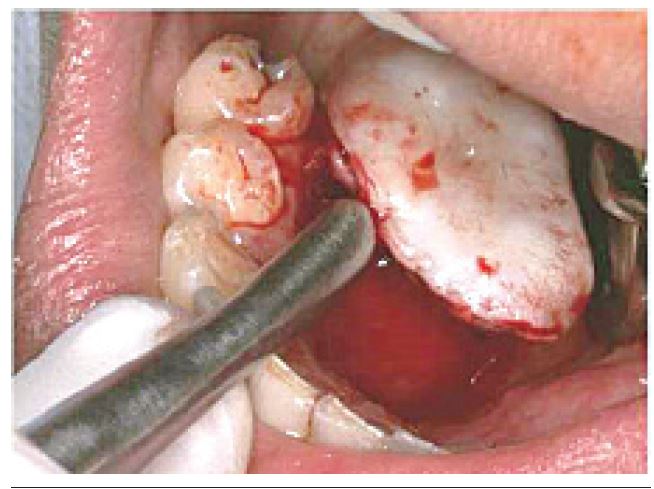

A. G. A., female patient, 27-years-old, Afro-Caucasian, attended the dental service complaining of increased volume on the lingual aspect of the right mandible, close to teeth 44 and 45. In the intraoral physical examination, a nodular lesion of approximately 3 cm in its greatest extent, pedunculated base, pale pink in color, similar to the adjacent mucosa was observed (Figure 1).

Ten days after the biopsy procedure, the patient returned to the service to complete the treatment, which consisted of surgical excision, followed by superficial osteotomy of the region of lingual side, where the lesion pedicle was located (it is believed to be the lesion originating tissue) (Figure 4).